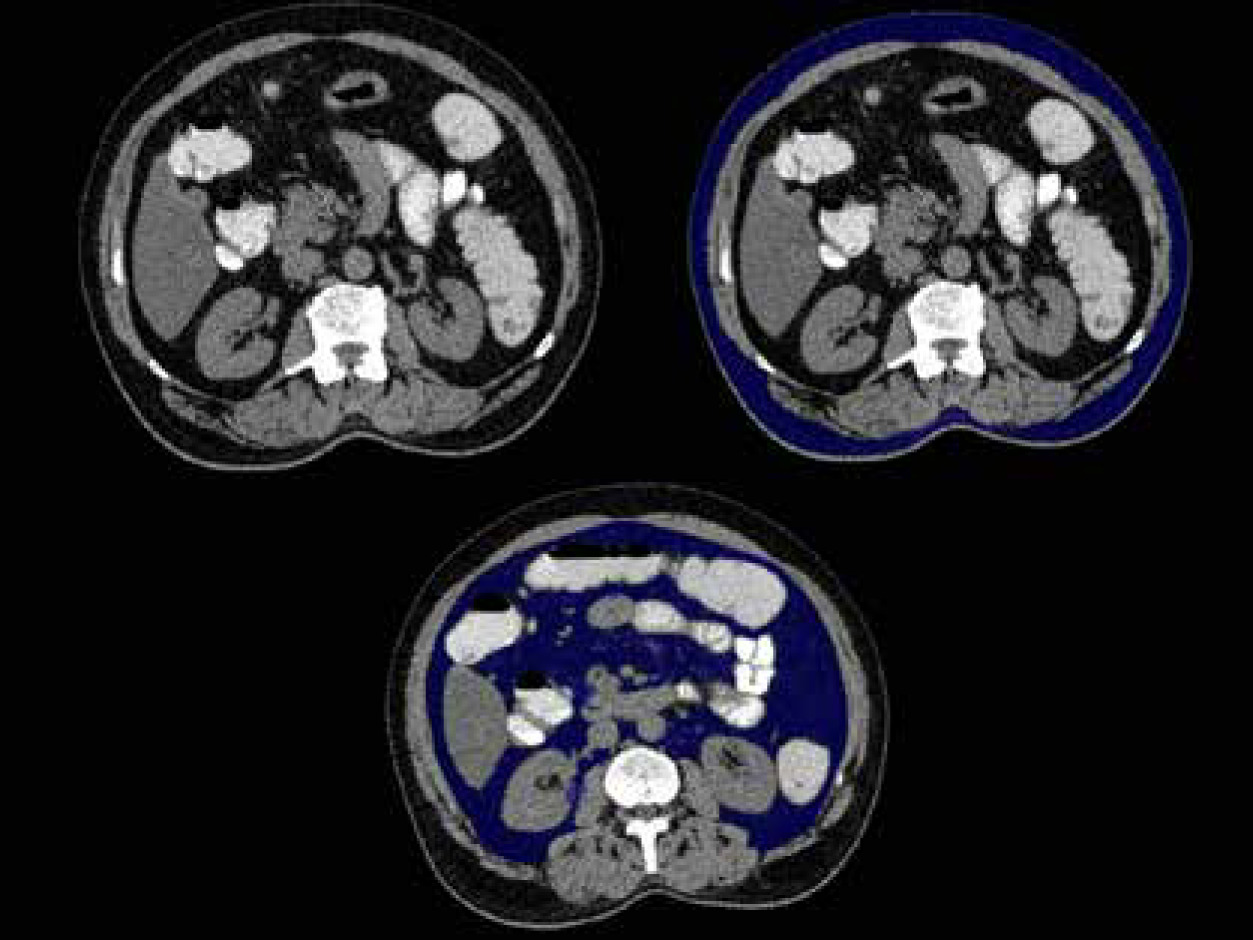

The studies were analysed by 2 radiologists, both experienced in abdominal imaging (3 and 10 years, respectively). Both radiologists were instructed to agree on a common segmentation technique to optimize results. Inter-rater correlation analysis was performed for a sample group, and there was no significant difference. In the pre-contrast CT scan, fat was identified as the pixels ranging from −250 to −50 Hounsfield units. The subcutaneous fat was described as the extraperitoneal fat between the muscles and the skin (Figure 1A). Visceral fat was defined as the intraperitoneal portion that had the same density as subcutaneous fat (Figure 1B). Total fat was the volume of fat combining the visceral and subcutaneous fat. A region growing segmentation algorithm was adopted. When an ROI was placed with the cursor over a certain grey-scale, the post processing software in the 128 slice MDCT scanner (Ingenuity Core 128 v3.5.7.25001; Philips Healthcare) was pre-programmed such that it selected all pixels in the grey level similar to the one selected. The software then provided the volume of the selected region – separate for the visceral and subcutaneous fat. The same is depicted in Figure 1.

Figure 1

Non-contrast abdominal computed tomography axial section at the level of L2-L3 intervertebral disc defining subcutaneous (A) and visceral fat (B) – blue coloured area